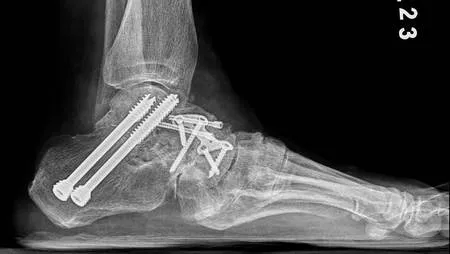

骨科醫師王禎麒表示,穆勒・魏斯氏症是一種少見的足弓結構畸形,為後跟内翻合併扁平足。此外舟狀骨成因除了外傷、過度使用,因遺傳或先天舟狀骨發育不全,皆是穆勒・魏斯氏症的好發族群。初期疼痛較輕微的患者可以透過客製化鞋墊將受力平均分散加上復健治療,避免加劇舟狀骨產生位移,但病程若進展成持續性疼痛、無法以正常步態行走的話就須透過手術治療。手術方式為將壞死的骨頭移除後,將其他骨頭復位,再取自體髂骨或是以大體老師捐贈的骨頭補在病灶處,加上鋼釘、鋼板讓骨頭更有支撐性,藉由「關節融合手術」將足踝骨骼融合固定。手術成功率約九成且幾乎不會復發,術後待骨頭品質穩定,須搭配助行器復健,訓練肌力、關節活動度。